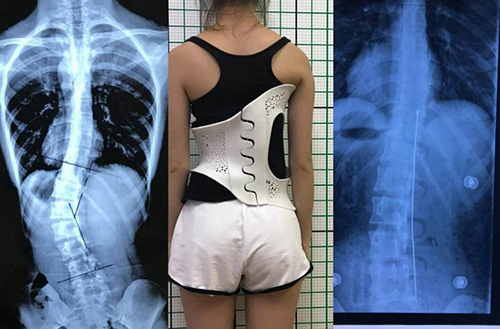

此外,在外固定支具研制方面,3D打印所起到的作用也不容忽視。對于意外摔傷導(dǎo)致骨折的患者來說,適宜的熱塑夾板、可卸式泡沫夾板、高分子夾板等外固定支具,有助于幫助患者快速恢復(fù),并降低發(fā)生二次骨折的風險。

(3D掃描和3D打印技術(shù)輔助制造的個性化脊柱矯正支具)